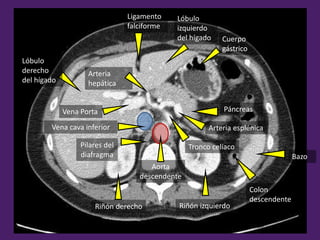

Ligamento

falciforme

Vena Porta

Bazo

Aorta

descendente

Vena cava inferior

Pilares del

diafragma

Lóbulo

izquierdo

del hígado

derecho

Riñón derecho Riñón izquierdo

Páncreas

Vesícula biliar

Píloro

Colon descendente

Antro

gástrico

Arteria

renal

izquierda

Vena renal izquierda

Arteria mesentérica superior

Primera porción

del duodeno